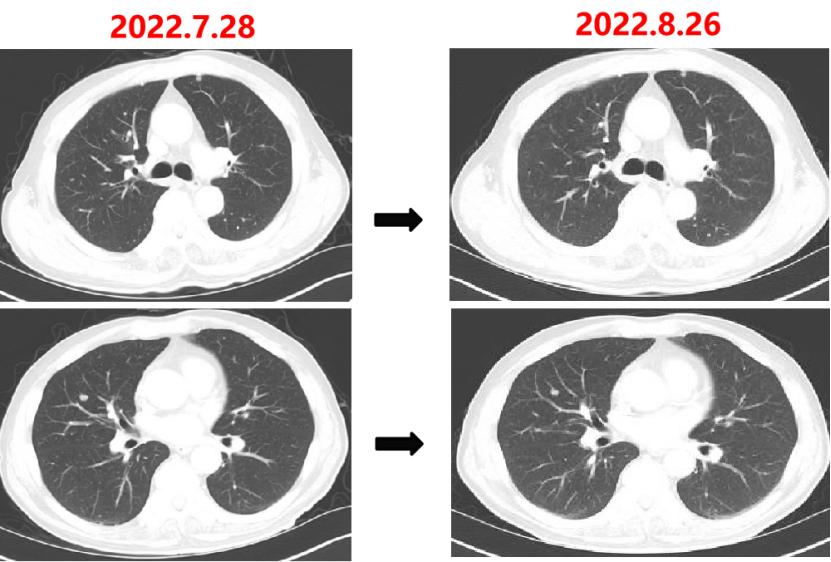

2022-07-06:骨髓抑制、腹泻,西妥昔单抗联合FOLFIRI方案治疗(西妥昔单抗900mg d1,伊立替康280mg d1,氟尿嘧啶0.7g iv 4.3g civ)。

疗效对比:

2022-07-27至今

给予贝伐珠单抗联合TAS-102治疗期间复查CT评估SD,胃肠道反应不重,骨髓抑制Ⅰ度,耐受性尚可。